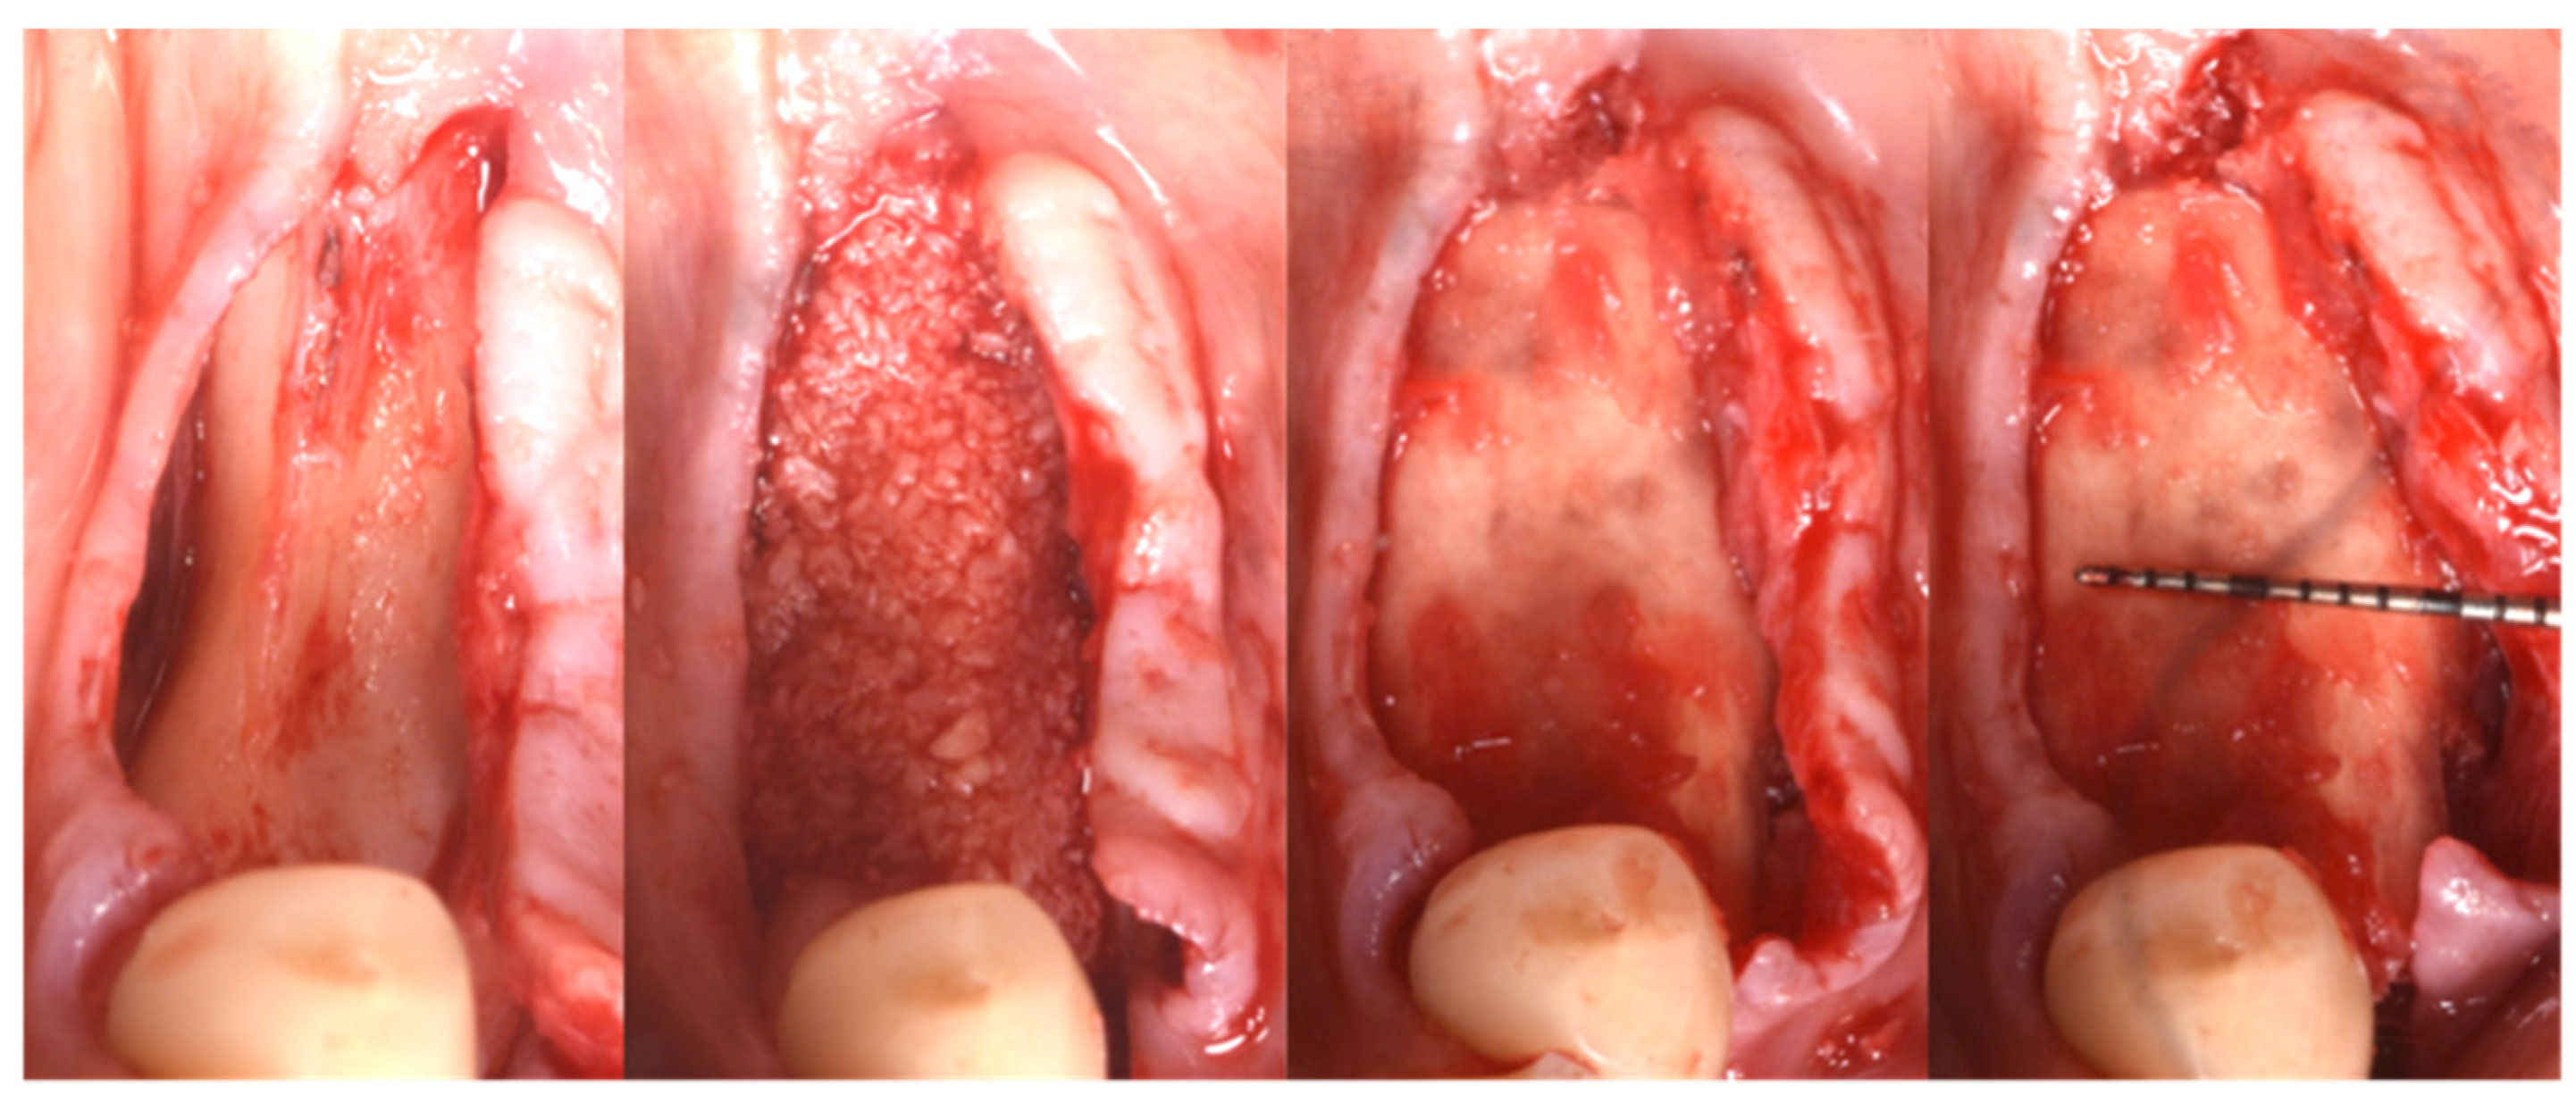

Following local anesthesia (articaine 40 mg with adrenaline 1:200,000), a full-thickness flap was elevated both in the buccal and lingual aspects after a straight incision with a number 12 surgical scalpel. The atrophic ridge was then exposed to allow some autogenous collection from the lingual side. The harvested bone grafts were mixed with the blood clot, the collagenated xenograft, and the fibrin glue (Tisseel®, Baxter, Rome, Italy). The compound was applied as a small consecutive addition to the edentulous ridge, creating a completely new, much larger, and more stable ridge (Figure 6). Passivation of both buccal and lingual flaps was achieved through a soft brushing technique as described by Ronda and Stacchi [30], a very atraumatic way to coronally advance the soft tissue to protect the new volume.

Figure 6.

Guided Bone Regeneration. Flex Cortical Sheet (FCS) was positioned to cover the bone grafts.

The FCS sheet (Osteoxenon®, Flex Cortical Sheet, Bioteck SpA, Arcugnano, Italy) was shaped and trimmed to match the dimension of the regenerated area. The FCS was first tried in place and then glued in its final position to cover the grafts. The final width of the regenerated surgical site was 10 mm (Figure 5).

The final assessment showed both vertical and horizontal gains immediately after the surgical procedure (Figure 7). The profile of the atrophic ridge has turned from concave to convex.

Figure 7.

Comparison between the edentulous ridge before the surgery and immediately after the bone augmentation procedure.